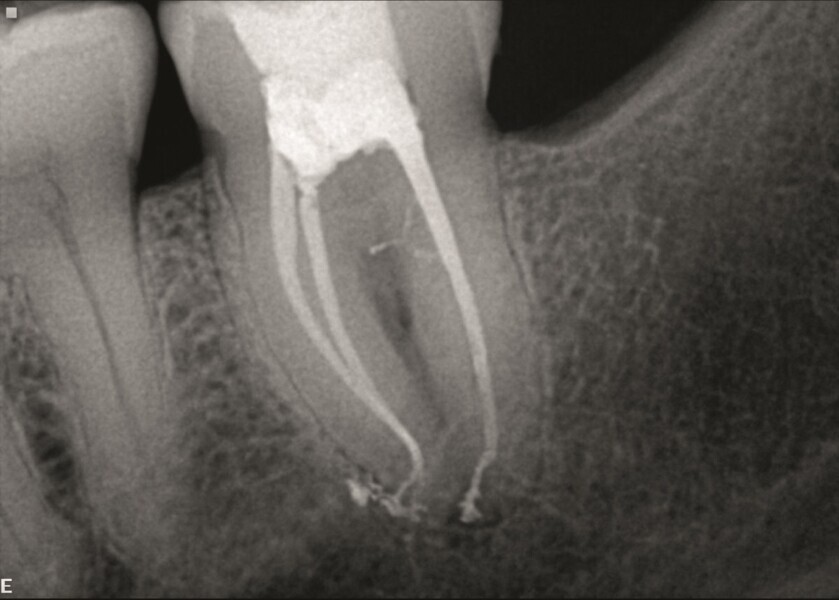

Toutes ces données sont précieuses pour choisir une séquence de limes nécessaire à la mise en forme et au nettoyage des canaux radiculaires. Le choix s’est porté sur les limes Traverse et ZenFlex de Kerr Dental (Fig. 5). Dans la racine distale, la lime 30/.04 n’a pas été utilisée dans les deux derniers millimètres, de façon à éviter toute déformation de cette zone. L’irrigation a été effectuée selon la technique dite « Séquence Sleiman » (article publié dans roots magazine 1/2014). L’obturation tridimensionnelle des canaux a été effectuée avec le système d’obturation éléments IC (Kerr Dental ; Fig. 6).

Les radiographies prises immédiatement après le traitement ont confirmé que tous les canaux étaient parfaitement obturés et scellés (Figs. 7a–c)